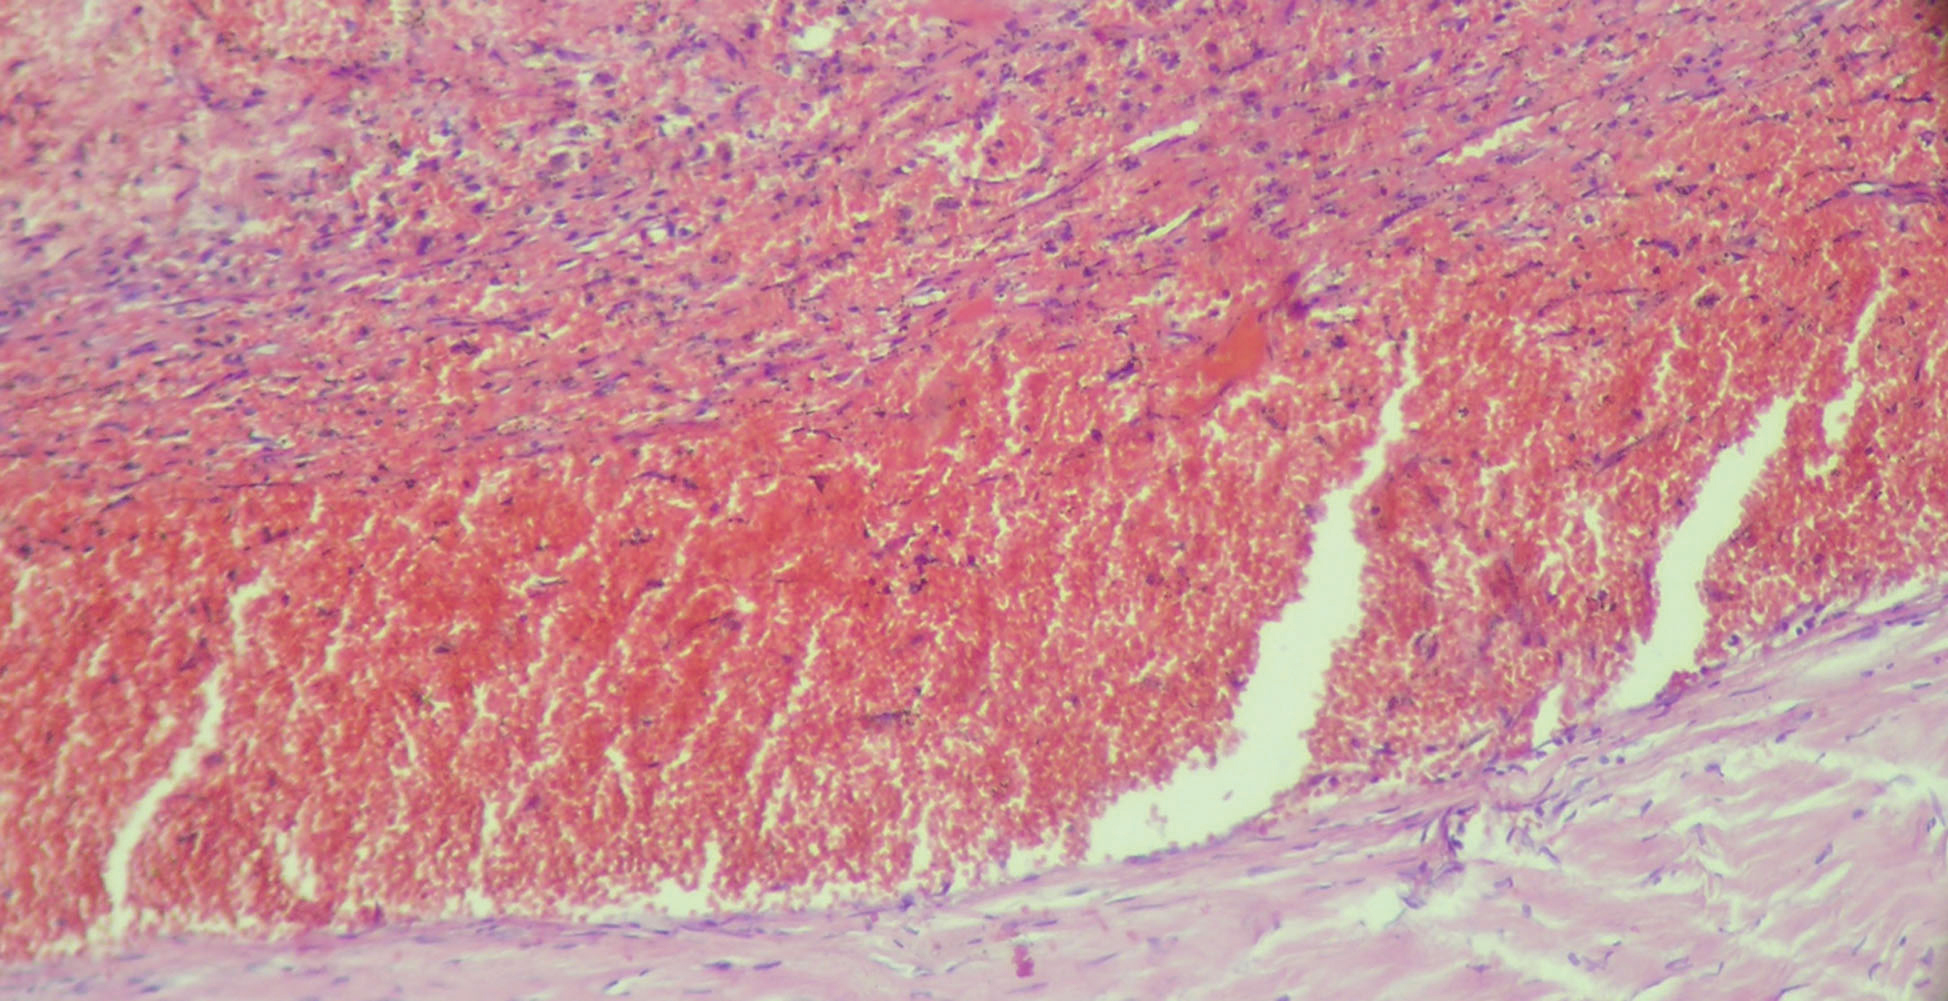

Стабильно организованные СГ представляют собой конечный этап естественной эволюции субдурального кровоизлияния, характеризующийся полным отсутствием содержимого гематомы и завершенностью организации ее капсулы. Чаще всего морфологические эквиваленты стабильно организованных СГ представляют собой сохранившиеся на субдуральной поверхности ТМО в исходе естественной эволюции гематом элементы их капсул небольшой толщины с диссеминированным внеклеточным гемосидерозом и инволютивно-дистрофическими изменениями различной степени выраженности (рисунок 3). Капсулы СГ данного типа также отличаются отсутствием стратификации, воспалительной инфильтрации и ВИК и небольшим удельным объемом сосудистого компонента. Подобные остаточные явления нами было предложено именовать очаговым субдуральным фиброзом ТМО [1].

Рисунок 3. Капсула стабильно организованной СГ. Окраска гематоксилином и эозином. 129х.